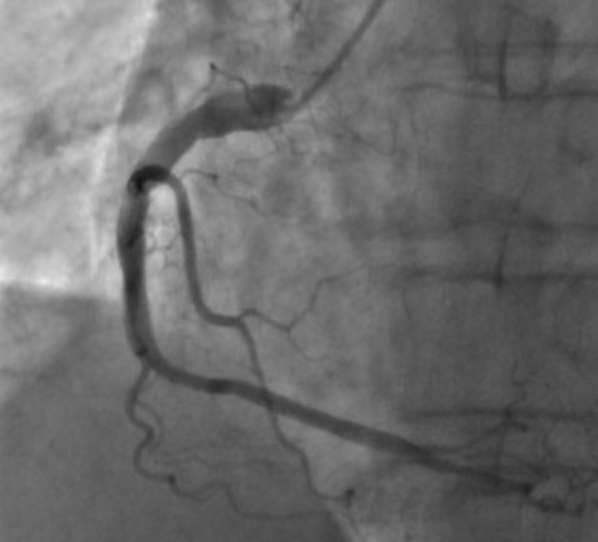

2023年09月14日下午4时35分,69岁的张大爷打牌中突然胸部闷痛,出大汗,就像是全身被浇了一盆凉水一样,非常难受。他电话联系家属乘车送我院胸痛中心。16:58到达医院大门,17:03查心电图示:窦性心律,Ⅱ、Ⅲ、AVF、V3R、V4R、V5R、V1-V4导联ST段抬高,T波高尖置。考虑急性ST段抬高型右室心肌梗死。立即给予心梗急救药物嚼服,吸氧、心电监护、建立静脉通道等紧急抢救措施。张大爷突然意识丧失,呼之不应,心电监护示室颤波形,先后进行2次紧急除颤。安得英医师团队迅速确定手术方案,建议马上进行“经皮右侧桡动脉穿刺下冠状动脉造影术+冠脉介入治疗”。随之迅速转运病人至介入导管室,冠状动脉造影提示严重冠脉闭塞病变,右冠第1段100%闭塞病变(图1),伴高负荷血栓影,高生云医师团队随即右冠内血栓抽吸术、溶栓术,打通闭塞血管(图2)。及时开通冠脉血流,为濒死的心肌重新供血(图3、图4)。从患者入门到开通血管仅用了47分钟。

图3 术后血流恢复正常

图4 术后一周后复查血流完全恢复正常

术后张大爷转CCU继续监护治疗,心内科医师团队会诊后考虑血栓负荷较重,制定了详尽、科学、精准的诊疗方案,为下一步的治疗提供了指导意见。经过心内科医护人员的精心治疗,张大爷生命体征平稳,各项监测指标趋于平稳,于09月22日复查冠脉造影示右冠血栓消失,第1段局部轻度扩张,前向血流恢复TIMI 3级。择日张大爷顺利出院。